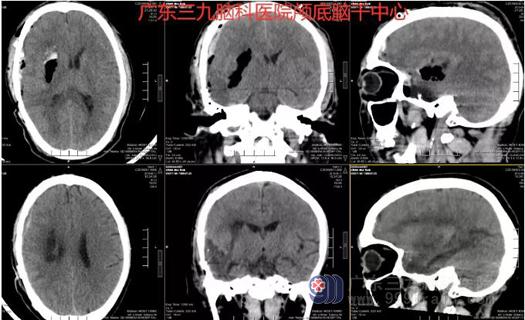

接诊后,立即完善相关检查,CT及CTA示右侧颞叶新增团片状高密度影,范围约7.2*5.3*2.4CM,体积约25ml,这正是导致陈先生突发意识不清的元凶。神经外一科团队随即为其安排了紧急手术,清除颅内血肿,切除了畸形血管。

术前CT及CTA示右侧颞叶新增团片状高密度影,范围约7.2*5.3*2.4CM,体积约25ml。

术前术后CT检查示右侧颞叶动静脉畸形切除术后改变。